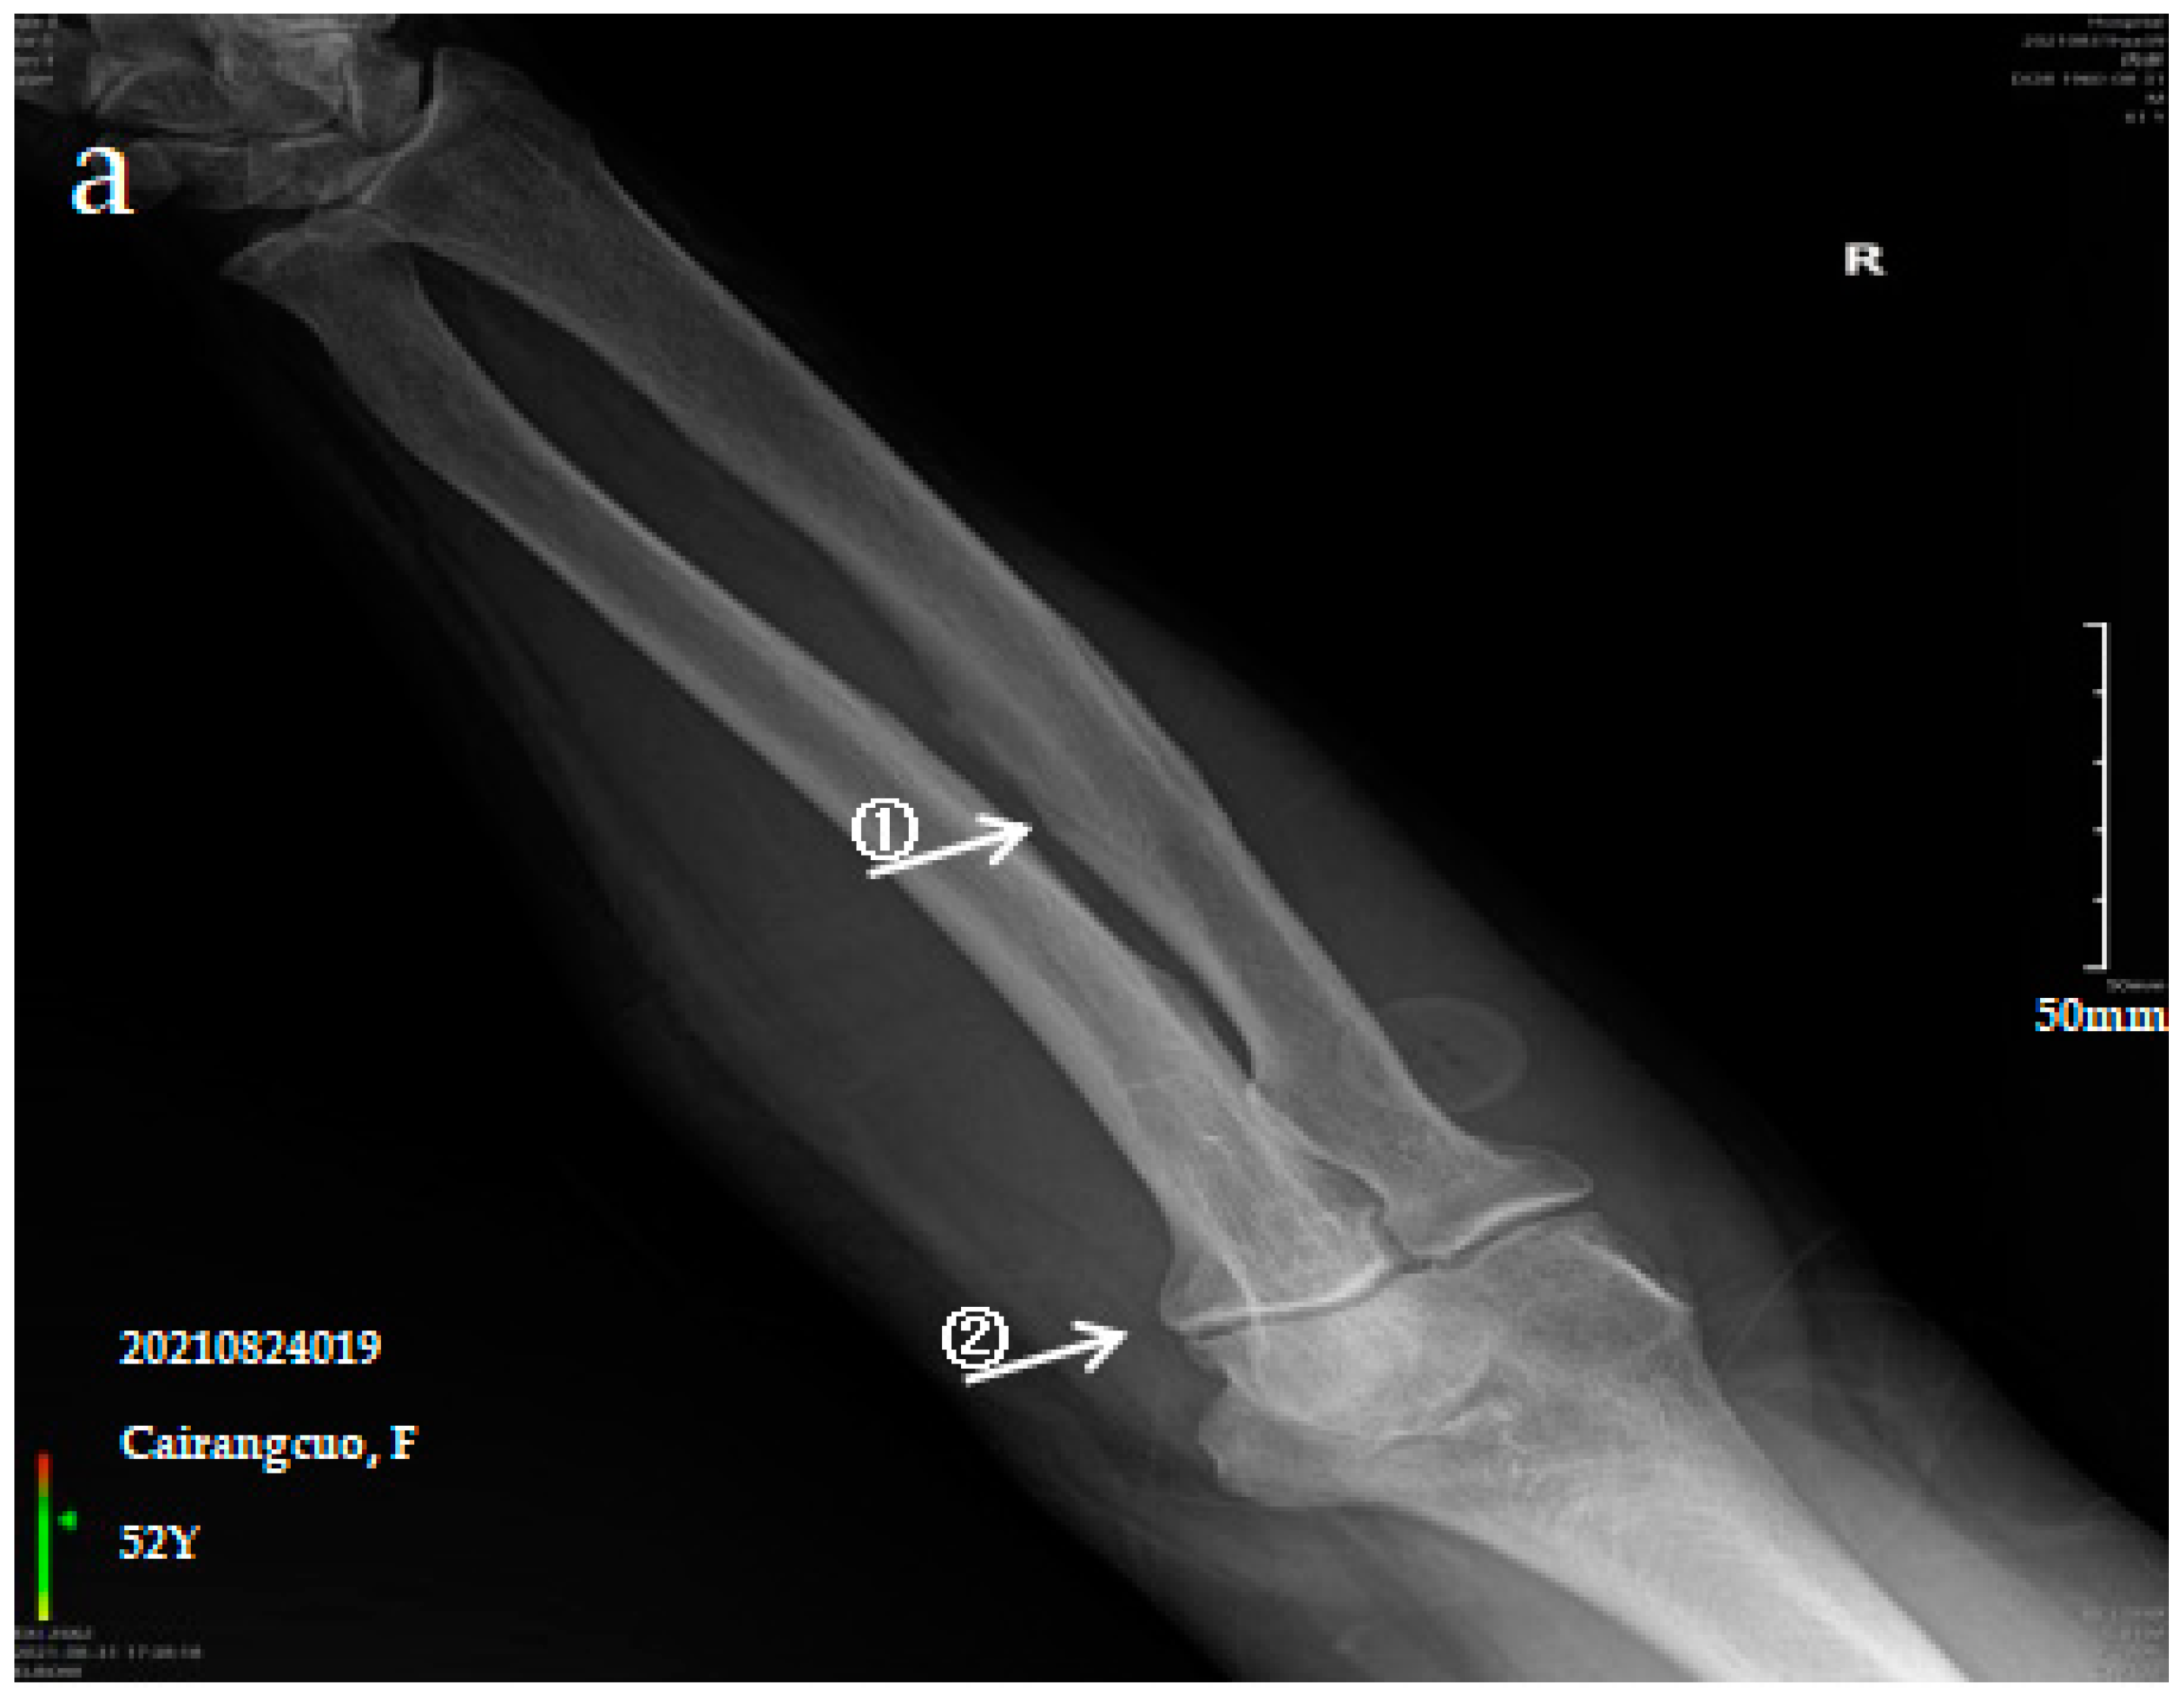

Figure 1.

X-ray imaging of SF patients. The anteroposterior actinogram of the upper limb (a) and both lower limbs (b) of patient with mild SF, the anteroposterior actinogram of the upper limb (c) and both lower limbs (d) of patient with moderate SF, the anteroposterior actinogram of the upper limb (e) and both lower limbs (f) of patient with severe SF. ①: ossification of interosseous membrane; ②: degeneration of the elbow joint; ③: Ossification shadow; ④: Ossification of knee joint capsule; ⑤: ossification of soleus tendon.

The patient is a 71-year-old male with severe bone and joint pain, limited activity and no ability to work. The anteroposterior actinogram of the upper limb (Figure 1e) shows obvious ossification of the interosseous membrane of the ulna and radius, forming a large fin-like ossification near the ulna and radius. The pronator teres muscle tendon shows obvious ossification, and a stalactite ossification shadow can be seen in the radial head. There is obvious degeneration of the elbow joint. The anteroposterior actinogram of both lower limbs (Figure 1f) shows ossification of the tibiofibular interosseous membrane, with a colliculus appearance. The peroneus longus tendons show obvious ossification, as do the soleus tendon, knee joint capsule and tibial collateral ligament.

Ossification of the interosseous membrane has a high incidence and specificity in SF and is one of the important diagnostic signs of SF. Ossification of the interosseous membrane was more obvious in patients with severe SF than in those with mild or moderate SF.